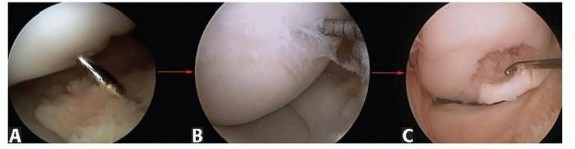

Chapter 40 Arthroscopic Treatment of Elbow Loss of Motion Laith M. Al-Shihabi Chris Mellano Robert W. Wysocki…